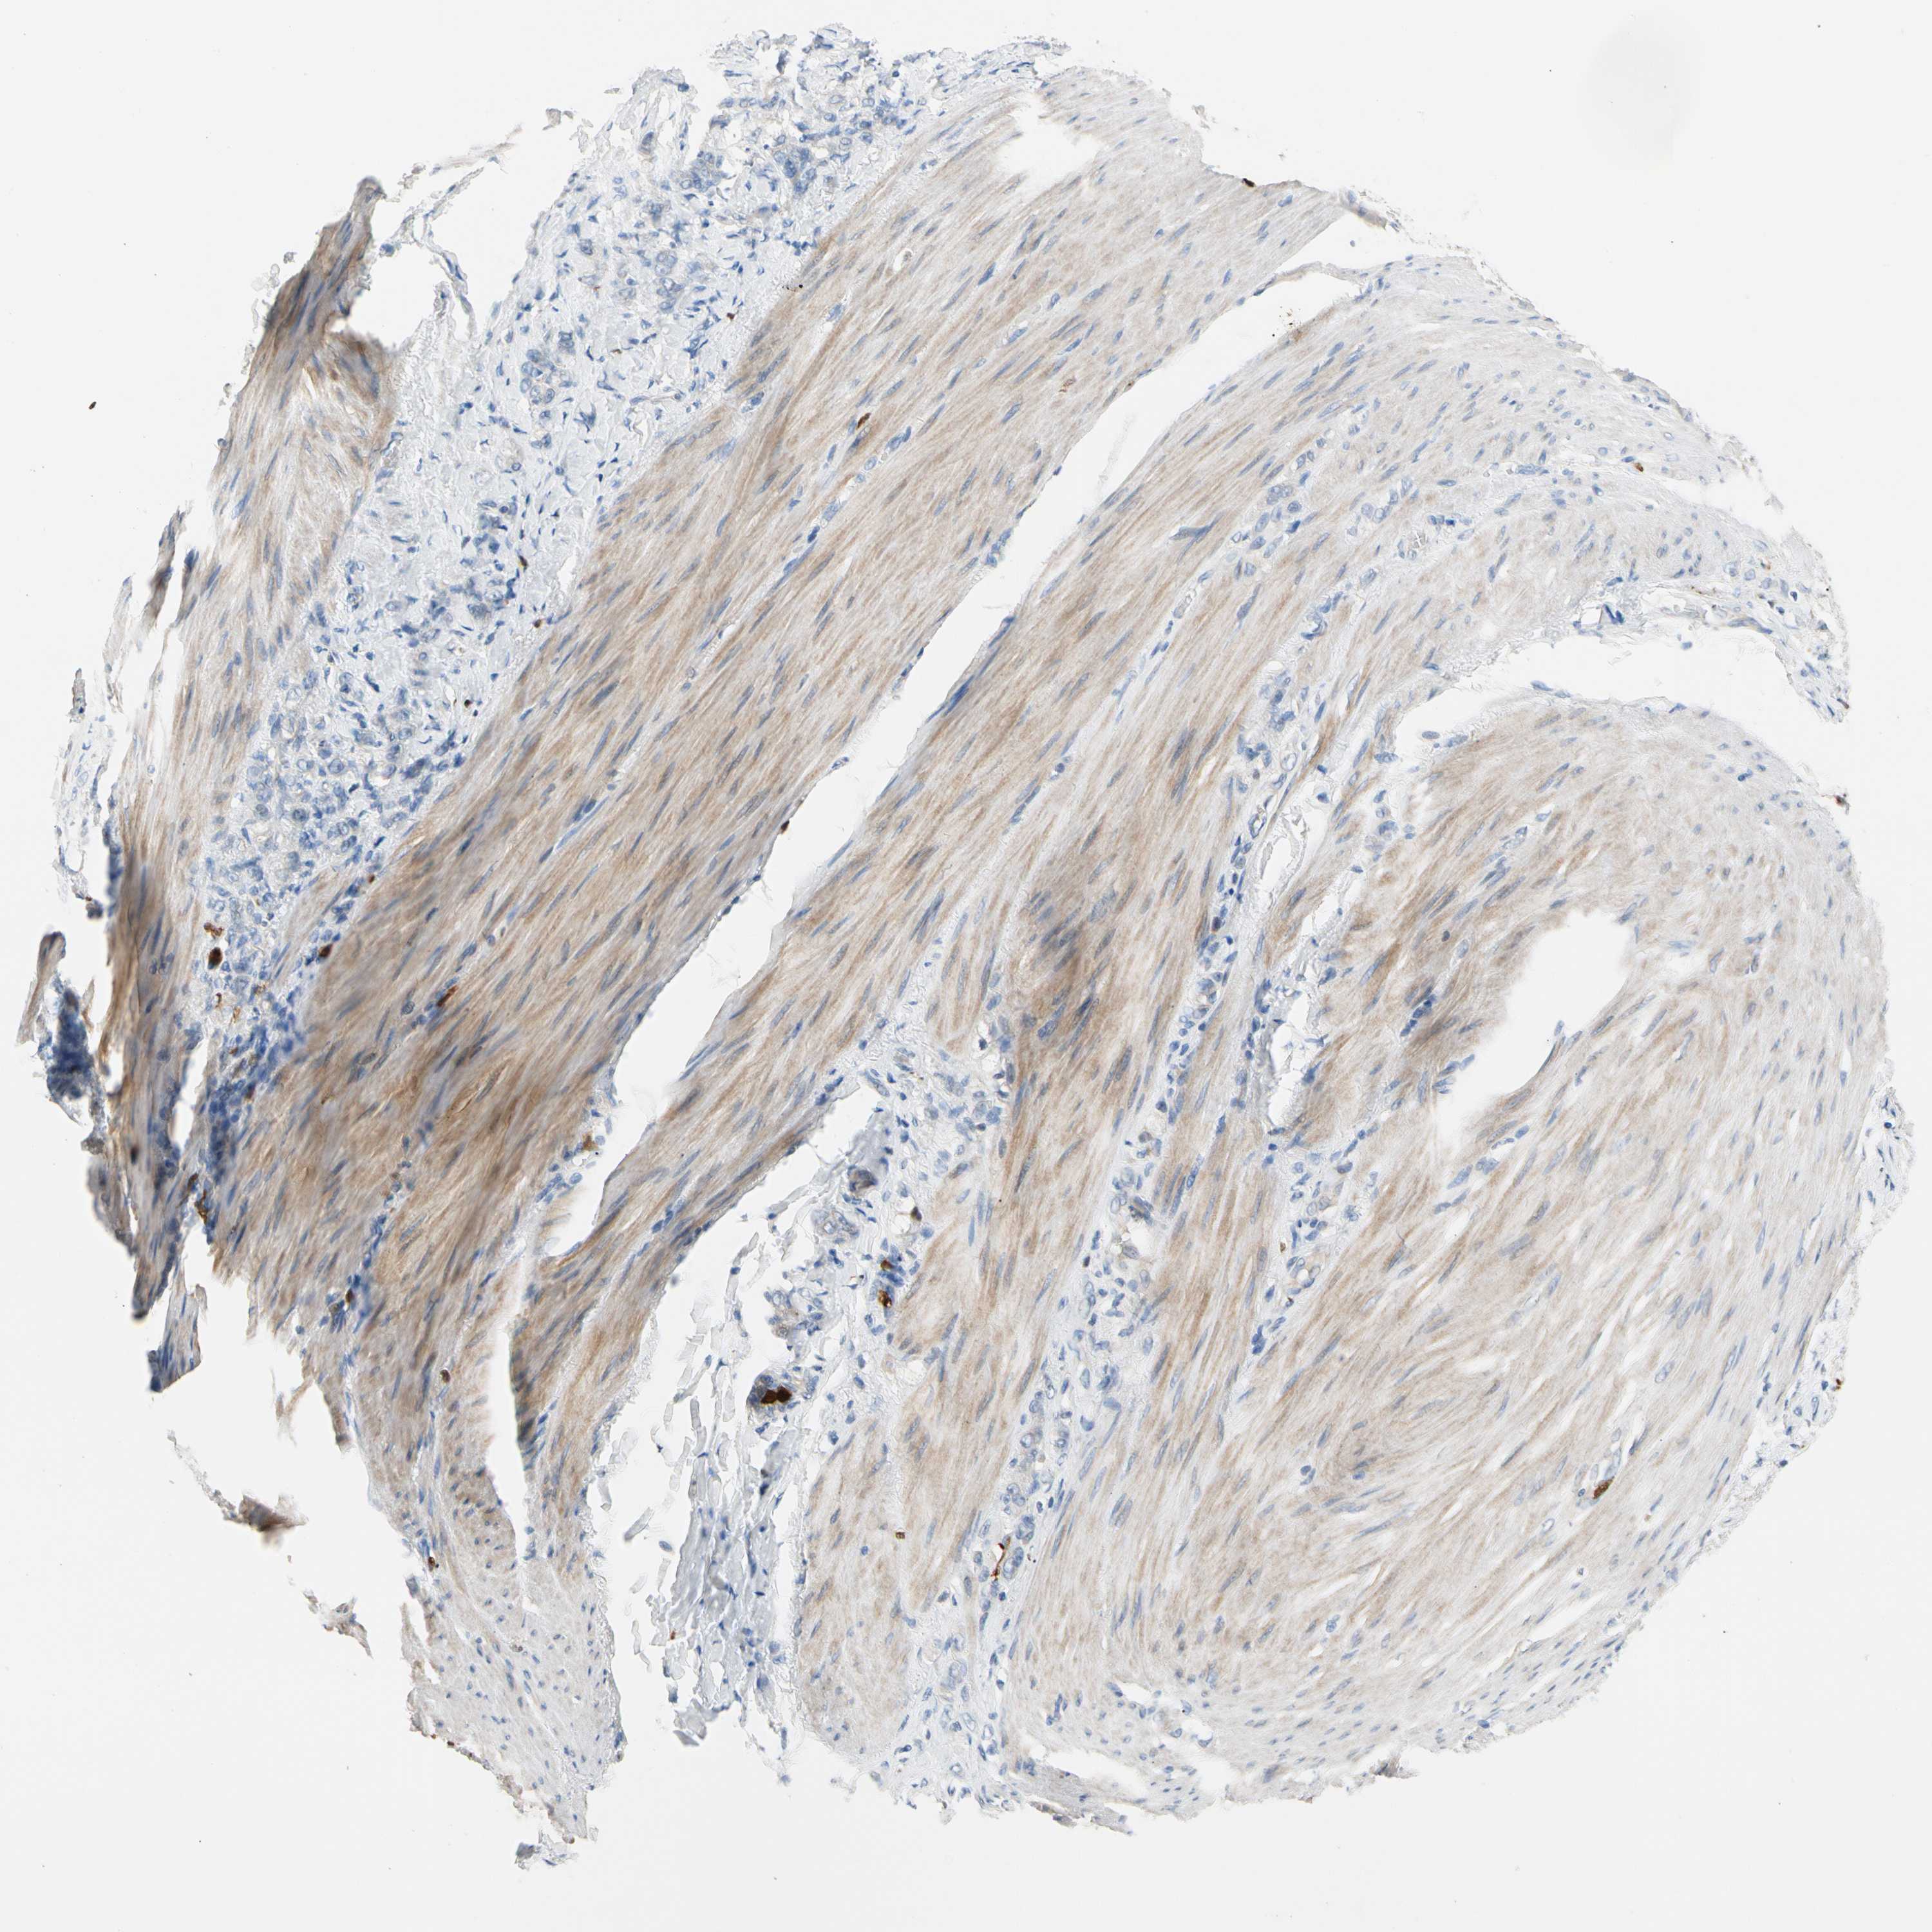

STOMACH CANCER - Protein expressioni

A mouse-over function shows sample information and annotation data. Click on an image to view it in a full screen mode. Samples can be filtered based on level of antibody staining by selecting one or several of the following categories: high, medium, low and not detected. The assay and annotation is described here.

Note that samples used for immunohistochemistry by the Human Protein Atlas do not correspond to samples in the TCGA dataset.

Antibody stainingi

Antibody staining in the annotated cell types in the current human tissue is reported as not detected, low, medium, or high, based on conventional immunohistochemistry profiling in selected tissues. This score is based on the combination of the staining intensity and fraction of stained cells.

Each image is clickable and will lead to virtual microscopy that enables deeper exploration of all samples and also displays staining intensity scores, fraction scores and subcellular localization as well as patient and tissue information for each sample.

Antibody HPA008052

Antibody CAB010277

Staining

High

Medium

Low

Not detected

Intensity

Strong

Moderate

Weak

Negative

Quantity

>75%

75%-25%

<25%

None

Location

Nuclear

Cytoplasmic/membranous

Cytoplasmic/membranous,nuclear

Adenocarcinoma, NOS

Adenocarcinoma, High grade